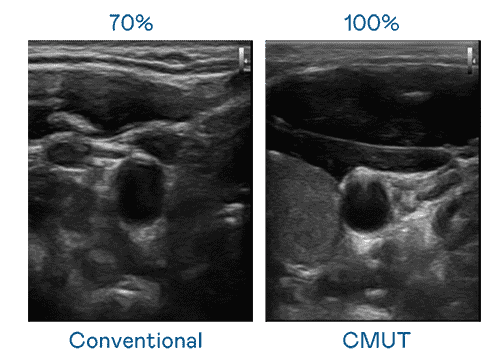

CMUT 技术是一种用电容式微机电元件来产生超音波讯号的技术。。。。与传统 PZT 压电式技术相比,,,CMUT 频宽增加 30%,,,更宽频的超音波讯号让影像解析度大幅提升,,,是实现高影像品质医疗超音波扫描、、、、促进精准医疗发展的关键技术。。

大频宽带来超清晰影像

超音波影像的解析度高低,,,首先取决于探头能发出的讯号频宽。。www.z6.com CMUT 可提供高清晰的超音波讯号,,,提供高频宽、、、高灵敏度、、、、影像纹理细节更高的超音波影像,,,,协助医护人员缩短影像判读时间及利用精准的医疗影像进行诊断。。